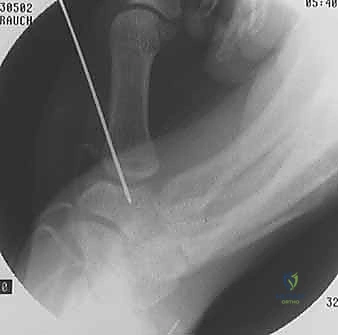

- Pilon Fracture ORIF: An Intraoperative Masterclass in Distal Tibial Reconstruction

- Open Reduction and Internal Fixation of Ulnar Styloid, Head, and Metadiaphyseal Fractures